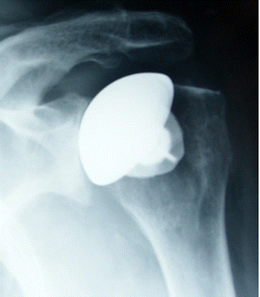

Fig. 2

figure 2

The nucleus presented very good primary stability with considerable osteointegration and no signs of looseningᅟ

No haematomas, infections, complex regional pain syndromes, nor nervous complications were observed during the follow-up period. At last follow-up, two patients had been re-operated upon. One was a revision (6 months after surgery) of a hemiarthroplasty in a 78 year-old man (primary osteoarthritis), due to residual pain and radiographic signs of periprosthetic osteolysis (Fig. 1). The nucleus presented very good primary stability with considerable osteointegration and no signs of loosening (Fig. 2). A posteriori the patient was diagnosed with glenoditis. Another was a revision (3 years after surgery) of a total shoulder replacement in a 78 years-old woman to a reversed TSA, due to massive anterosuperior tear of the rotator cuff with pseudoparalysis of the shoulder. The nucleus also presented very good primary stability with no signs of loosening or macroscopic osteolysis.

Two patients required surgical revision. The first case was revised due to persistent pain and presence of glenoid radiolucencies that led to suspicions of early loosening. During the revision procedure, the nucleus appeared adequately fixed (Fig. 1). A posteriori, the diagnosis was early glenoid wear. The second case was revised for pseudopa-ralysis of the shoulder due to a massive anterosuperior tear of the rotator cuff. Again, during the revision procedure, the nucleus appeared adequately fixed. Both patients re-ceived a reversed TSA and their revision procedure was relatively simple because it did not involve extraction of a humeral stem, hence confirming the supposed benefits of stemless shoulder arthroplasty.